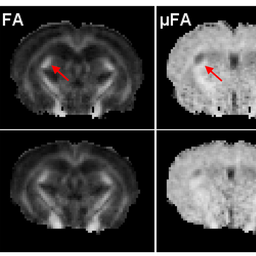

This paper compares two anisotropy metrics (measurements types)

in mouse brains.